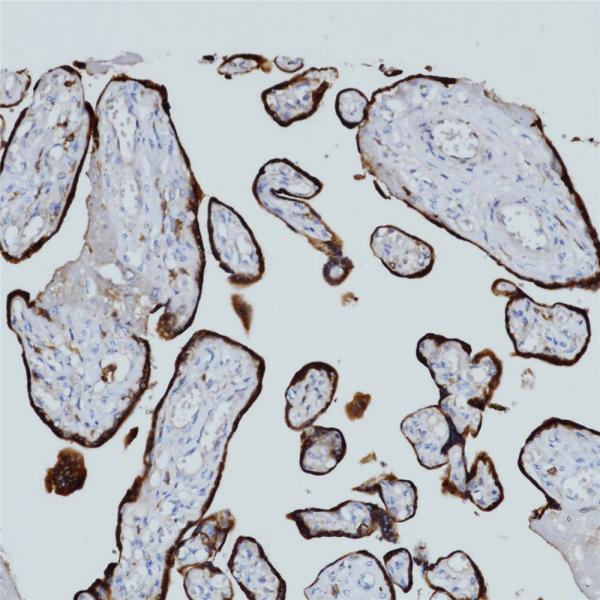

HLA-G

BP6247